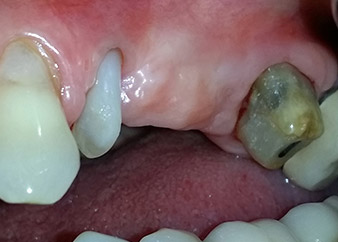

Two-months interim result

Figures 17 and 18 show the clinical result two months after the surgery. Tooth 24 exhibited reduced mobility of Miller class 1, and the soft tissues were free of inflammation. Probing was avoided at this point of time to prevent reinfection and to avoid violating the epithelial attachment. A control visit was scheduled for reentry and placement of healing abutments, six months after the insertion of the implants.

Two months after the surgery, the patient was pain-free.

Fig. 17: Two months after the surgery, the patient was pain-free and the area was free of inflammation.

after the surgery

Fig. 18: Tooth 24 now showed less mobility.